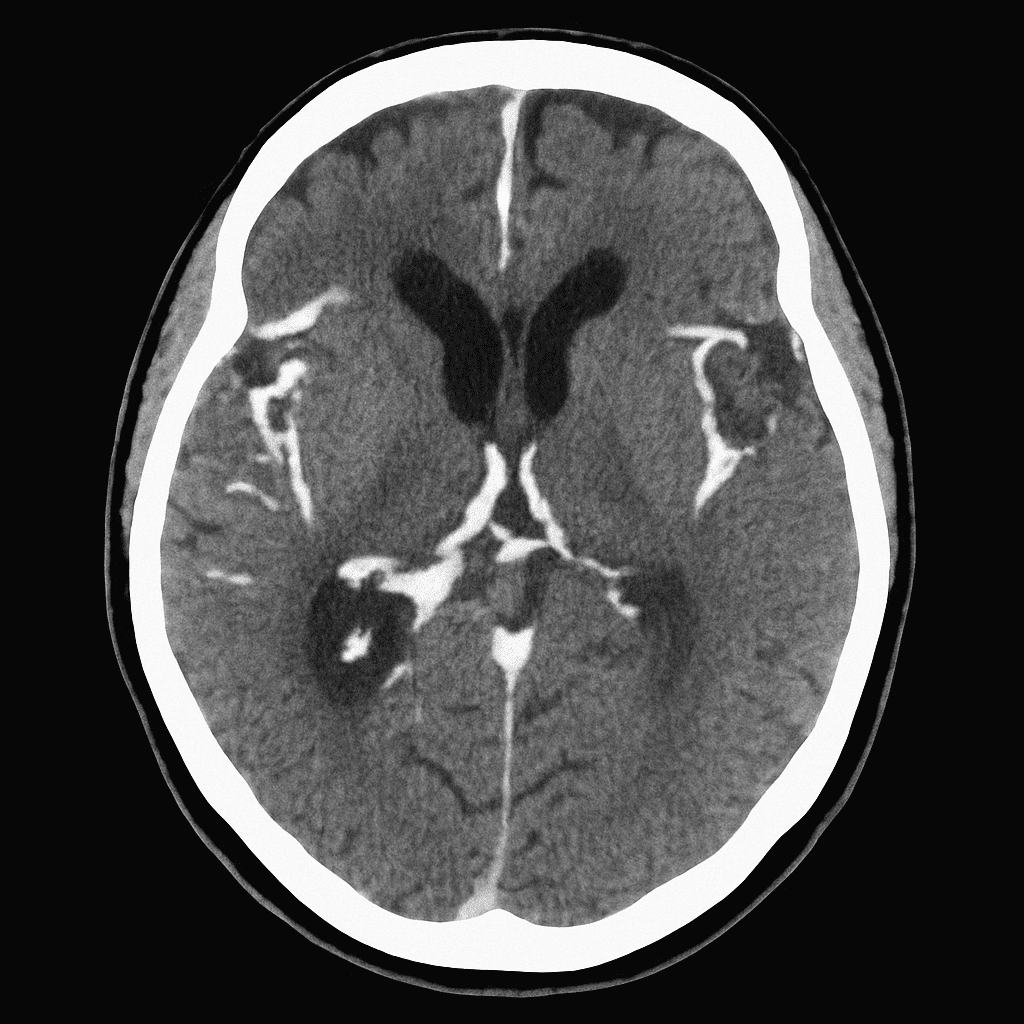

A 48-year-old woman presents to the emergency department with a sudden, severe headache that she describes as “the worst headache of my life.” The pain began abruptly while she was exercising at the gym. She vomited shortly after the onset and has been increasingly photophobic. On examination, she is alert but distressed. Neck flexion is painful, and her blood pressure is 162/98 mmHg. A non-contrast CT brain is performed and shown below.

Which of the following is the most likely diagnosis?

A) Acute migraine

B) Subarachnoid haemorrhage

C) Intracerebral haemorrhage

D) Viral meningitis

E) Acute ischaemic stroke